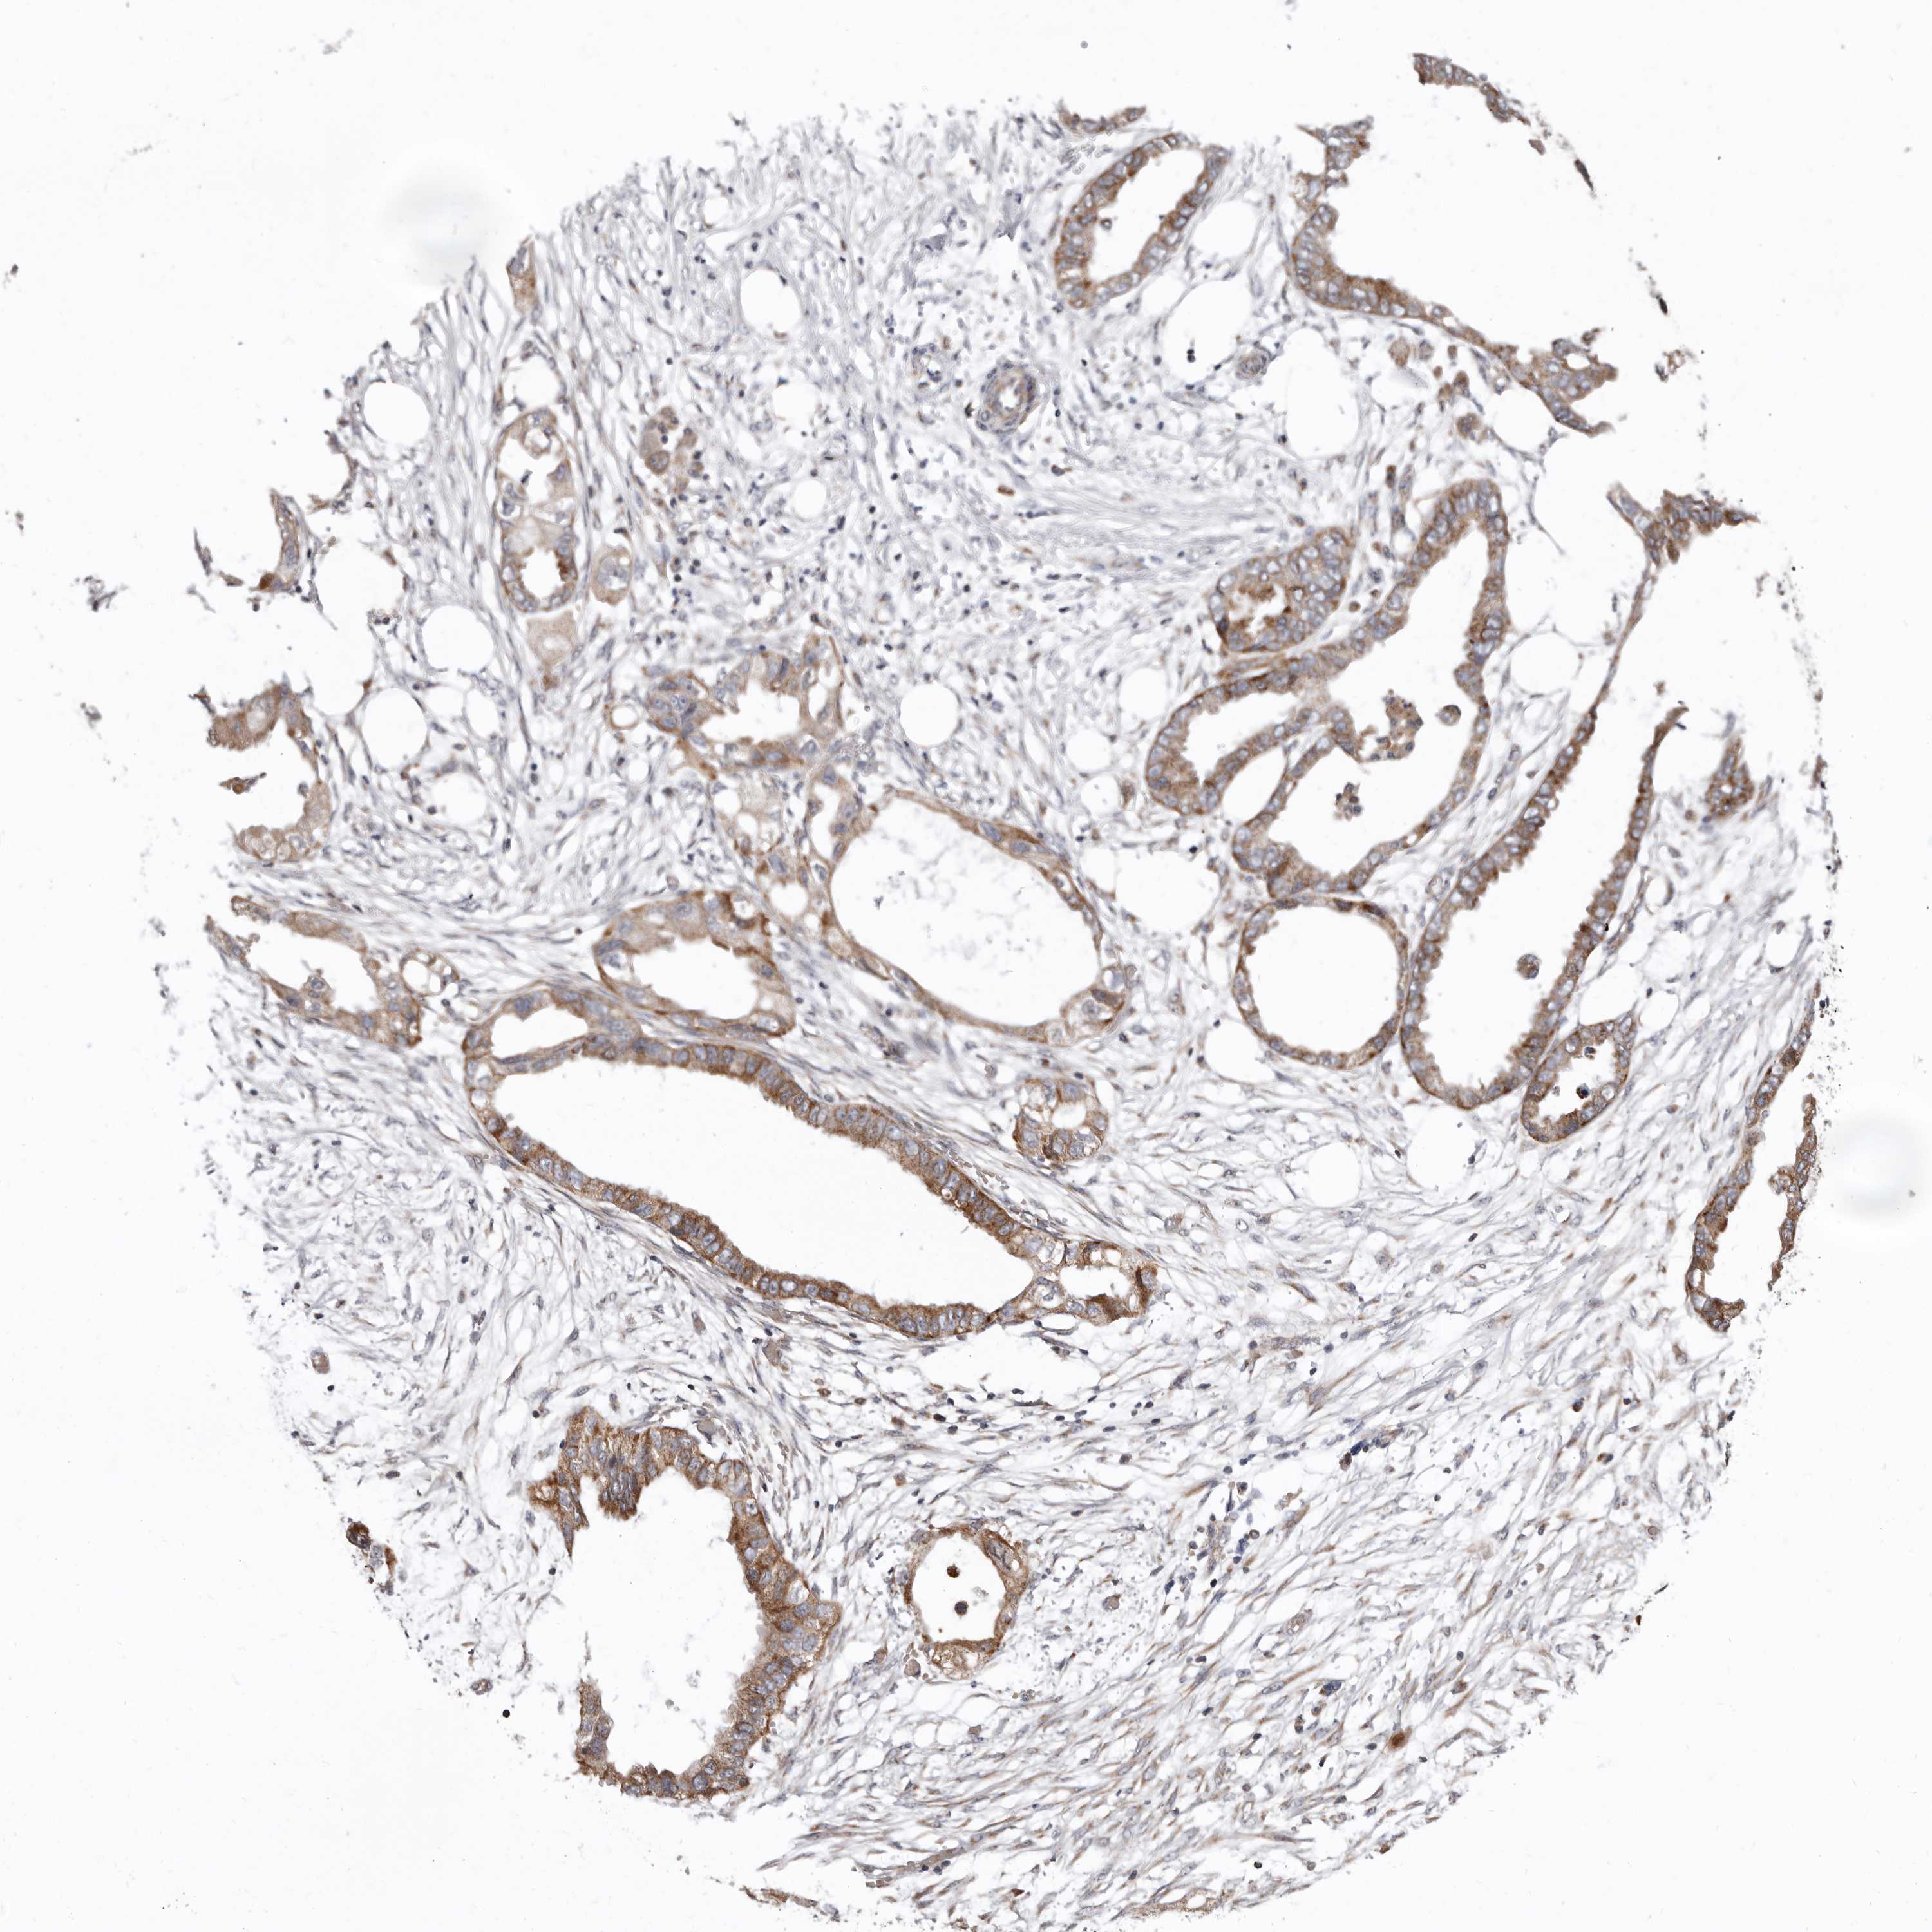

ENDOMETRIAL CANCER - Protein expressioni

A mouse-over function shows sample information and annotation data. Click on an image to view it in a full screen mode. Samples can be filtered based on level of antibody staining by selecting one or several of the following categories: high, medium, low and not detected. The assay and annotation is described here.

Note that samples used for immunohistochemistry by the Human Protein Atlas do not correspond to samples in the TCGA dataset.

Antibody stainingi

Antibody staining in the annotated cell types in the current human tissue is reported as not detected, low, medium, or high, based on conventional immunohistochemistry profiling in selected tissues. This score is based on the combination of the staining intensity and fraction of stained cells.

Each image is clickable and will lead to virtual microscopy that enables deeper exploration of all samples and also displays staining intensity scores, fraction scores and subcellular localization as well as patient and tissue information for each sample.

Antibody HPA029449

Antibody CAB055509

Staining

High

Medium

Low

Not detected

Intensity

Strong

Moderate

Weak

Negative

Quantity

>75%

75%-25%

<25%

None

Location

Nuclear

Cytoplasmic/membranous

Cytoplasmic/membranous,nuclear

Adenocarcinoma, NOS